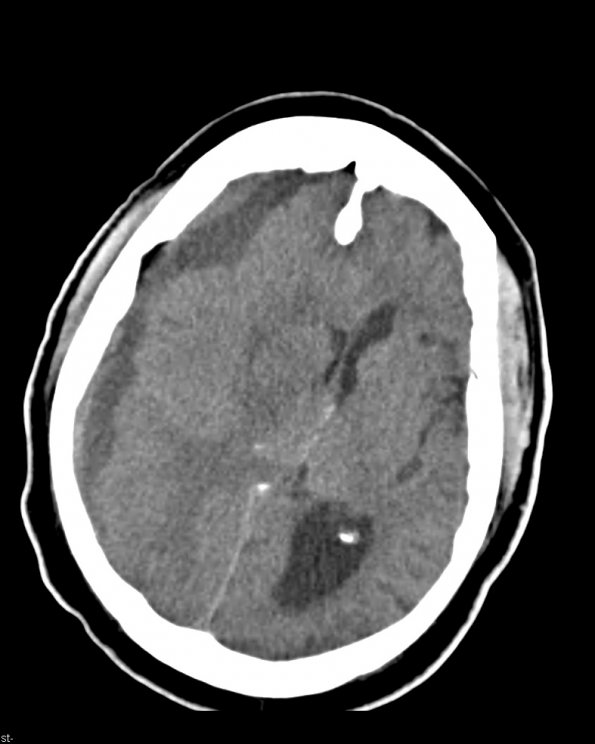

A CT image showing the right hemispheric subdural hematoma with left shift and collapse of the right lateral ventricle.